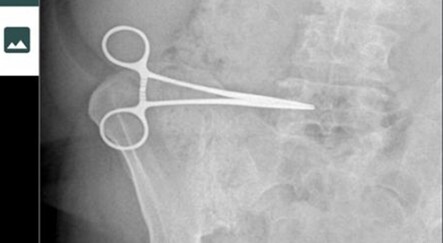

Güney Kore’de cerrahların kalifiyeli olmayan kişilerin ameliyatlara katılması ve çok sayıda ameliyatta sorun yaşanmasının ardından yeni bir tartışma başladı. Milletvekilleri ameliyathanelere güvenlik kamerası yerleştirilmesini oylayacak. Tasarının parlamento tarafından kabul edilmesi durumunda Güney Kore, ameliyathanelere güvenlik kamerası yerleştiren ilk ülkelerden biri olacak. Güvenlik kamerasının ameliyathanelerde bulundurulması konusu, 2016 yılında özel kliniklerde yapılan ölümle sonuçlanan bazı operasyonlarda cerrahların ameliyatlara hemşireler ile daha az başarılı doktorları görevlendirdiklerine yönelik suçlamaların yer aldığı davanın ardından gündeme geldi.

2016 yılında üniversite öğrencisi olan Kwon Dae-hee, geçirdiği çene ameliyatının ardından 49 günlük komanın ardından kan kaybı sonucu hayatını kaybetti. Oğlunun ölümünün ardından tek kişilik protesto başlatan Kwon’un annesi Lee Na-geum ise ameliyat görüntülerine ulaşmayı başardı. 7.5 saatlik ameliyatı defalarca izleyen anne Lee Na-geum, ameliyat öncesinde kendilerine yapılan açıklamanın aksine ameliyatın cerrah yerine hemşire ve stajyer doktor tarafından gerçekleştirildiğini tespit etti. Bu durumun Kwon Dae-hee’nin 3.5 litre kan kaybı sonucu hayatını kaybetmesine neden olduğunu ifade eden Kwon’un annesi elde ettiği görüntülerle hastaneye ve ameliyatı yapması gereken cerraha dava açtı. Dava sonucunda cerraha kasıtsız adam öldürme suçlaması ile 3 yıl hapis cezası verildi.